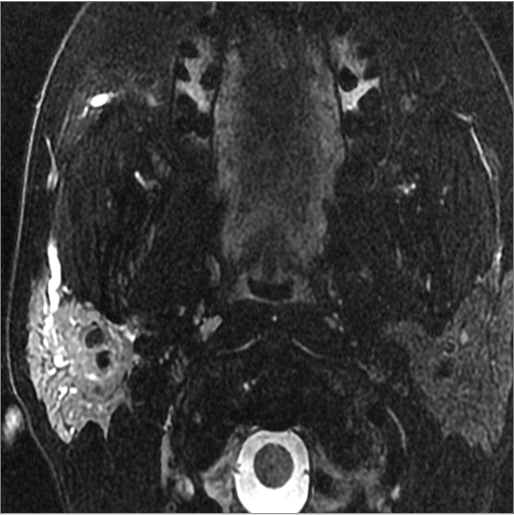

9 month old male presenting to the emergency room with poor feeding, fever, respiratory distress and possible retropharyngeal abscess or suppurative retropharyngeal adenitis.Exam

There is reactive retropharyngeal lymphadenopathy. |

There is suppurative retropharyngeal lymphadenopathy. |

Yes | NA |

If there is suppurative retropharyngeal adenopathy what is the maximum short axis dimension of the largest suppurative node. Measurement |

< 2cm | NA |

Pharyngitis with suppurative retropharyngeal adenitis.